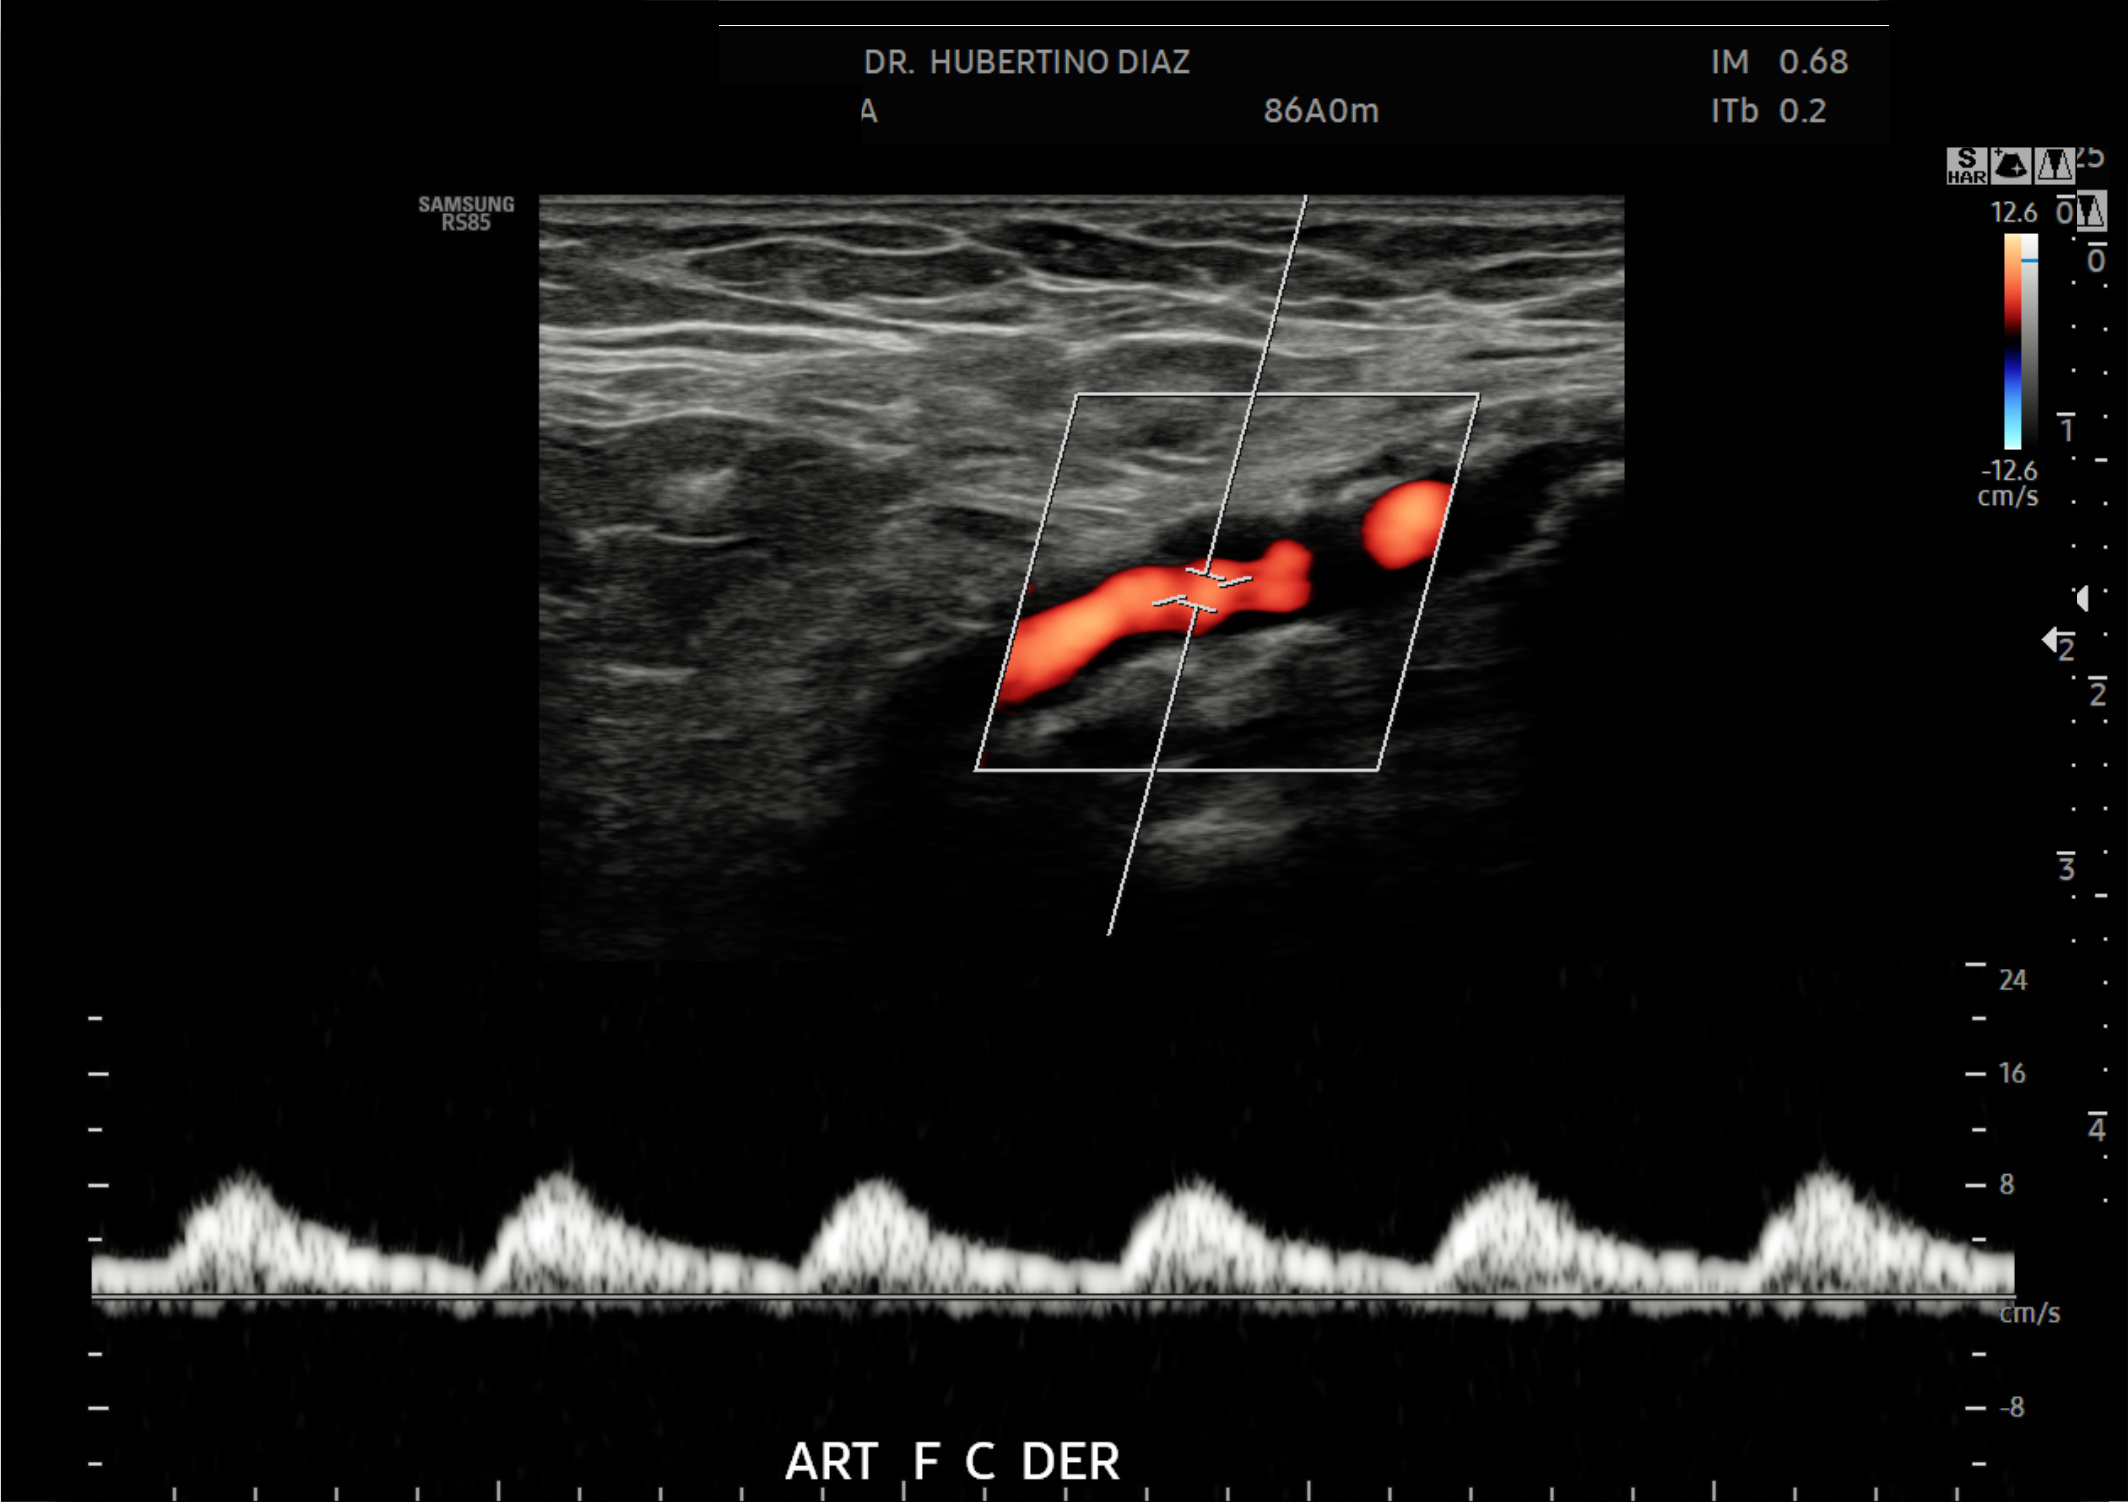

Trabajamos bajo la dirección del Dr. Hubertino Díaz, Director Médico de Diagnoimagen, referente en el Perú en ecografía avanzada, Doppler vascular y estudios de segunda opinión, reconocido por su trayectoria en diagnóstico ecográfico de alta complejidad.

En Diagnoimagen incorporamos un enfoque de ecografía multiparamétrica, combinando modo B, Doppler color, Doppler de microflujo y elastografía, lo que nos permite una evaluación más completa y precisa en múltiples patologías.

🔹La ecografía Doppler permite evaluar el flujo sanguíneo en arterias y venas, siendo fundamental para el diagnóstico de insuficiencia venosa, várices, trombosis, estenosis carotídea y patología hepática.